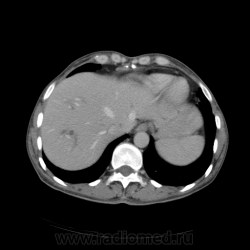

КТ ОБП - гепатомегалия, признаки панкреатита

МРТ ОБП - от 16.12.10 гепатомегалия, расширение панкреатических протоков.

Похоже на то, что все было списано на калькулезный холецистит. Наши морфологи пересмотрели стекла с гистологией и окончательно написали о наличие высокодефференцированной аденокарциноме. У меня только две мысли образования исходит из БДС или первичный рак 12п.к., хотя сейчас гадать бесполезно. 12п.к. циркулярно сужена.

Первичный рак ДПК очень редко встречается. Большинство опухолей, инфильтрирующих стенку ДПК, исходит все-таки из БДС.